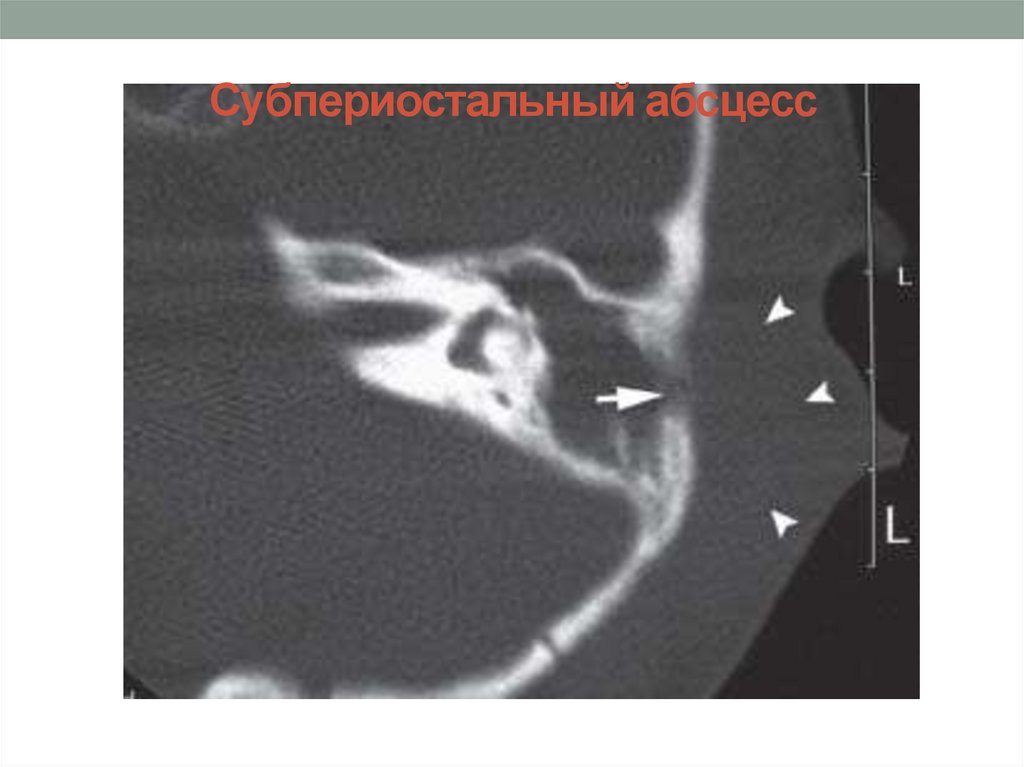

Субпериостальный абсцесс